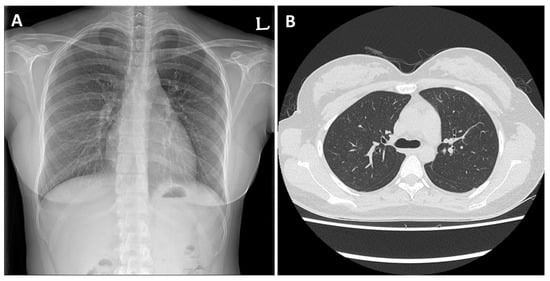

2. Case Presentation